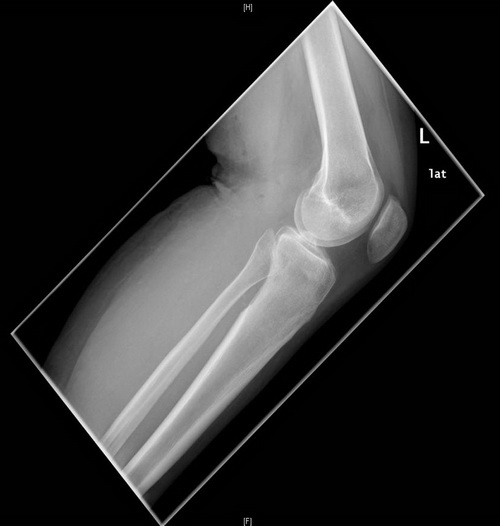

Röntgen in zwei Ebenen

Beachte die Aufhellung in der proximalen Tibia

Postoperative Röntgenkontrolle: Im Vergleich zu den Voraufnahmen zeigt sich, dass das bioptisch nachgewiesene Chondrosarkom im Bereich der proximalen Tibia dorsalseitig vollständig resiziert werden konnte. Kein Hinweis auf Fissuren oder Frakturen.